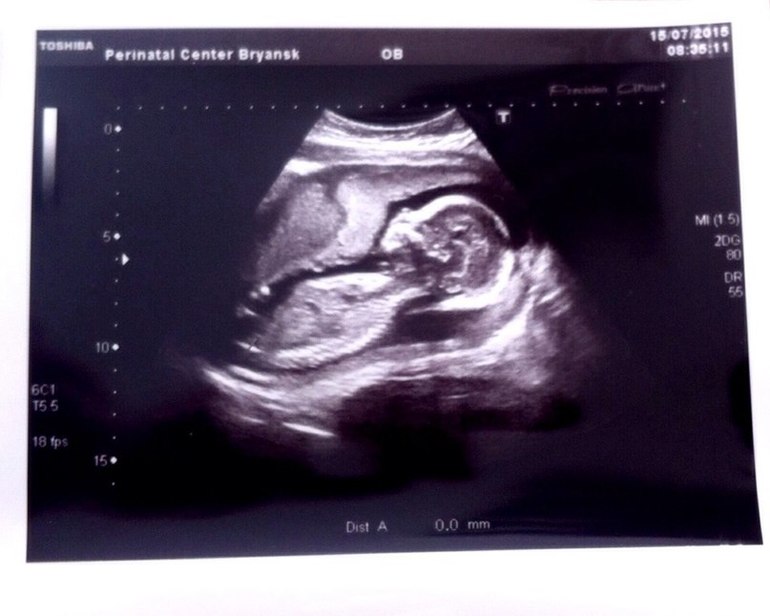

15-я неделя. Покалывания в области матки и в районе пупка.

Это матка растягивается или тонус? На узи была неделю назад, небольшой тонус по передней стенке, прикрепление по задней, но тогда и не было таких ощущений.